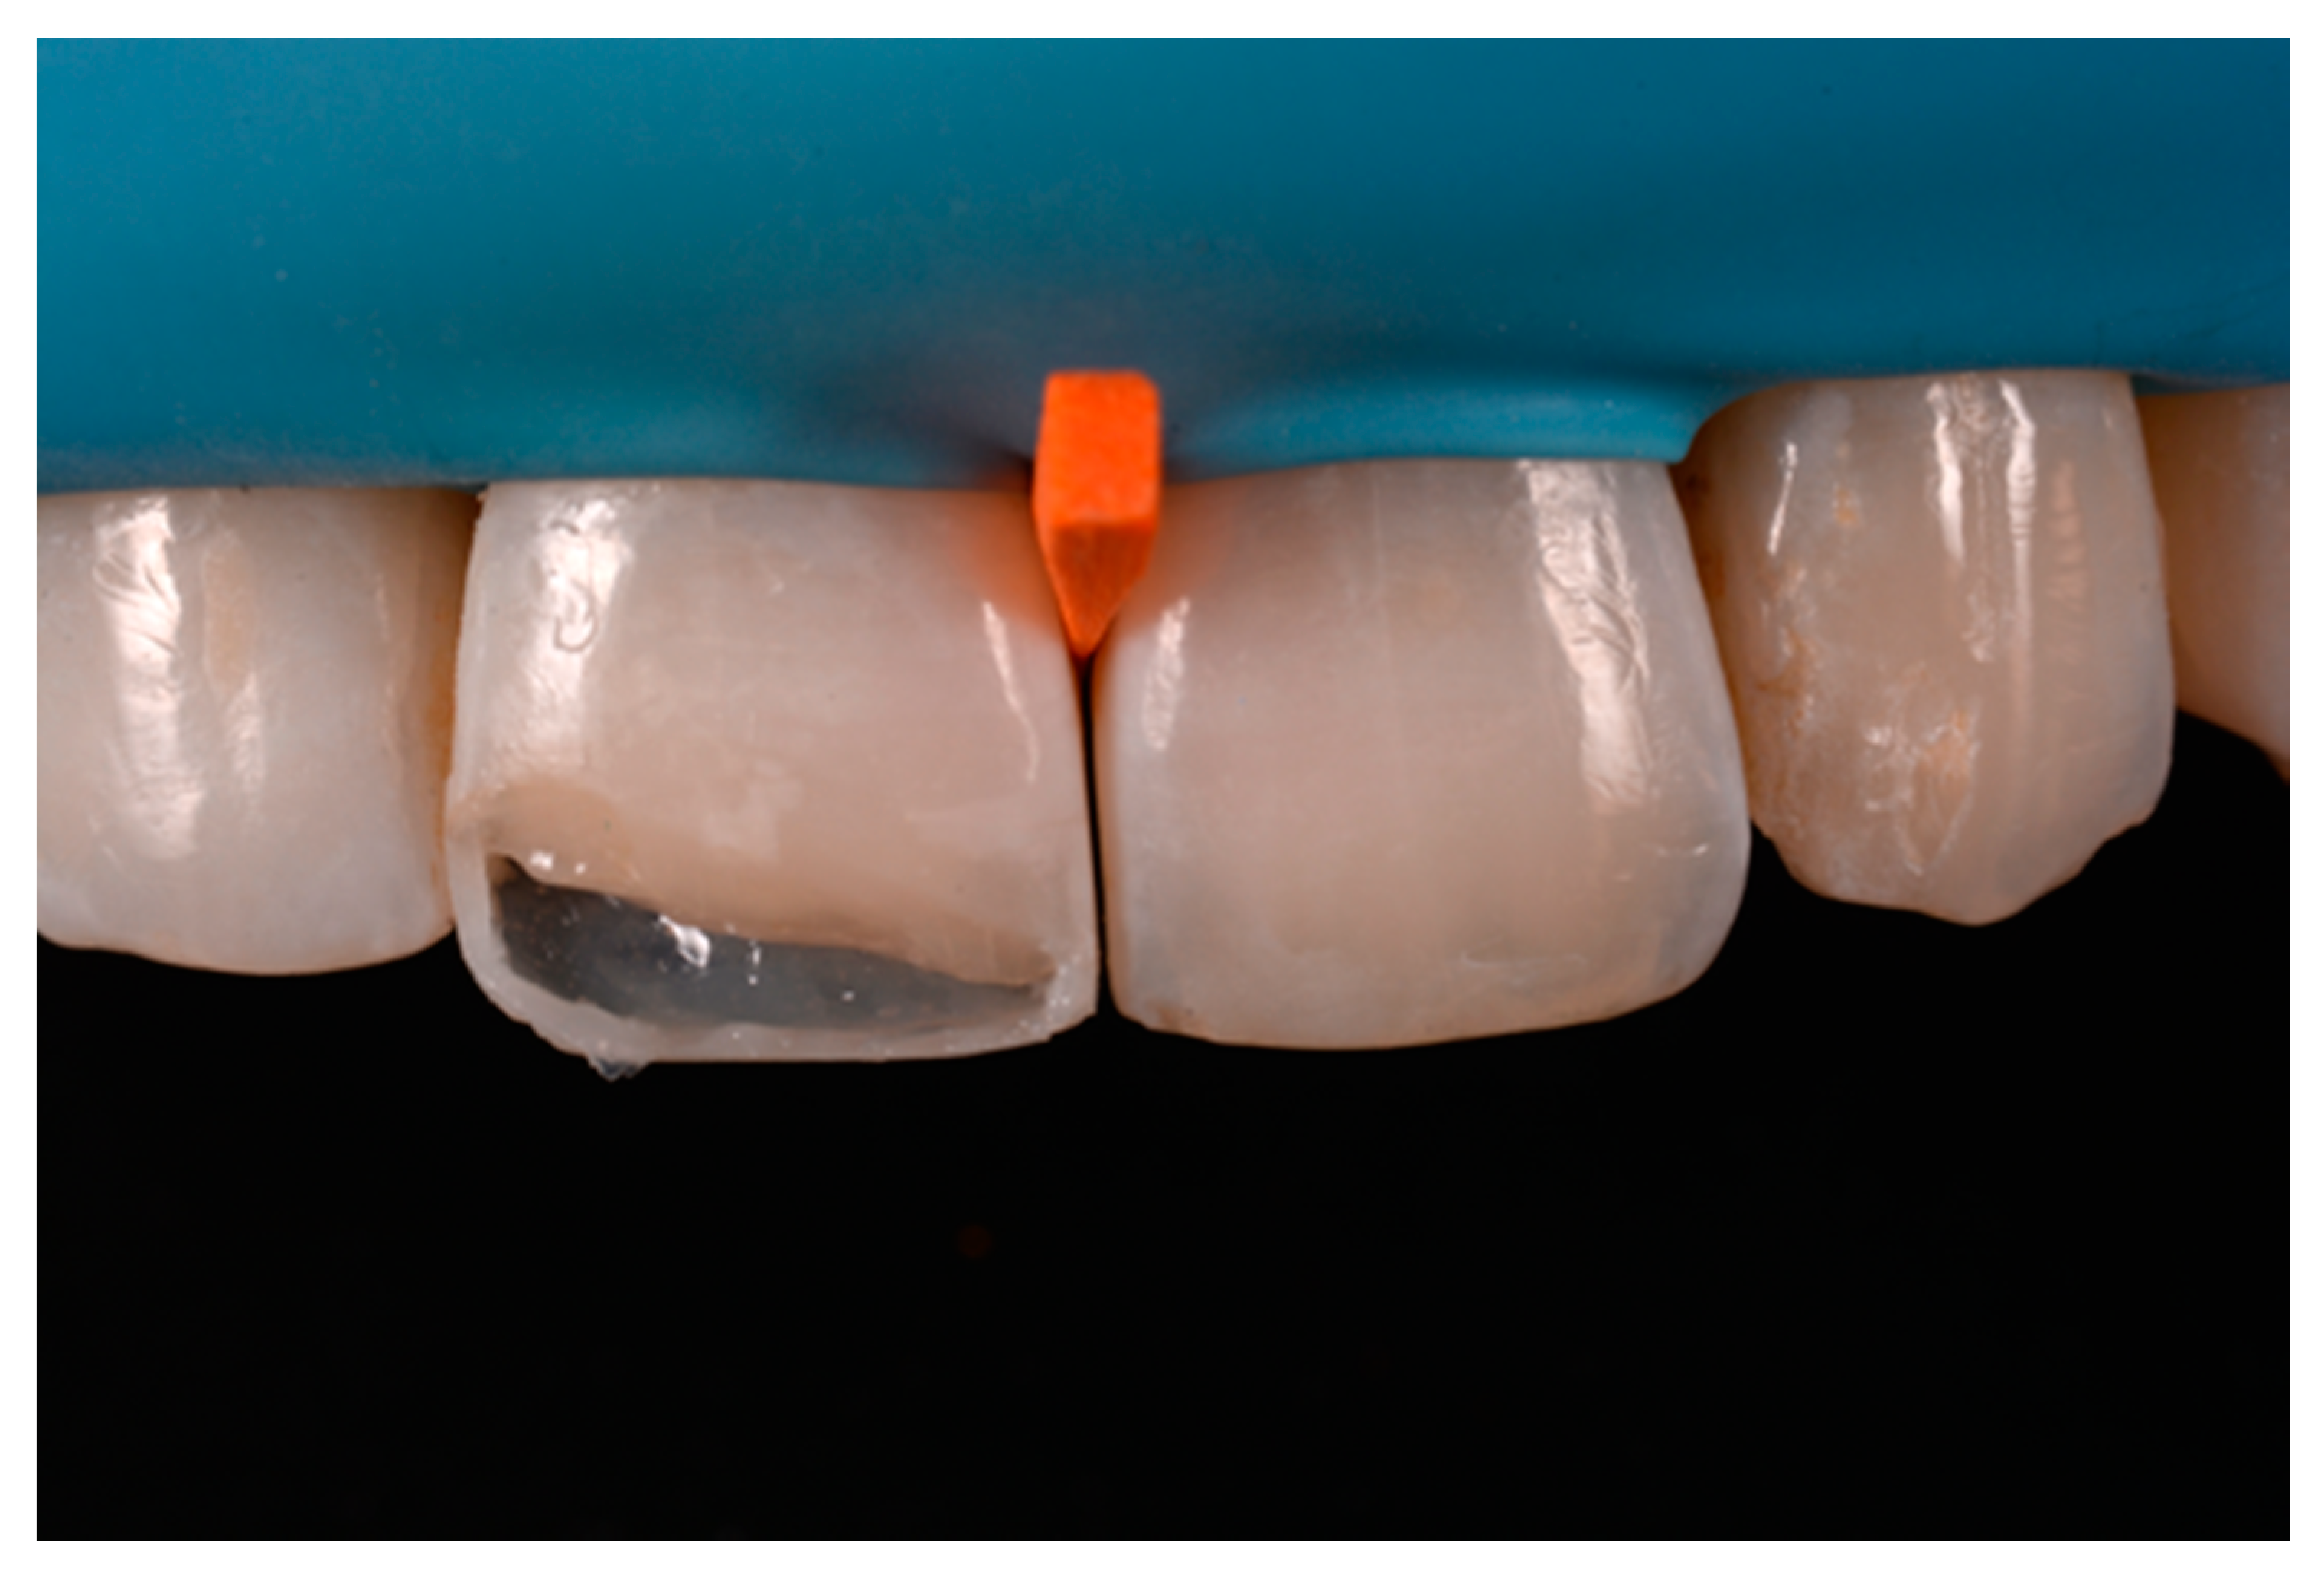

A healthy 38-year-old man referred to the dental office for the esthetic rehabilitation of left central maxillary incisor (Figure 41). Shade was selected as described in previous cases, using the button-try technique [14]. Isolation, preparation (Figure 42) and adhesive procedures were performed (Tokuyama Bond Force, Tokuyama Dental, Osaka, Japan). and Class III was restored on right central incisor (Asteria, A2B, Tokuyama Dental, Osaka, Japan). Frame was then completed on #2.1 (Figure 43) with the use of posterior sectional matrices using translucent and body material (Asteria, NE, A2B Tokuyama Dental, Osaka, Japan). After removing excesses both from the incisal margin and from the interproximal portion (Figure 44) silane and adhesive was applied strictly following the procedure described in Section 2.1.2. Dentinal body (Asteria, A2B, Tokuyama Dental, Osaka, Japan) was applied to reproduce internal anatomy (Figure 45) and then the external translucent enamel (Figure 46) (Asteria, NE, Tokuyama Dental, Osaka, Japan) was applied. The restoration shows good integration 6-months post-operative (Figure 47).

Figure 43.

The frame completed.

Figure 44.

The frame modified either in the incisal frame and in the interproximal wall.